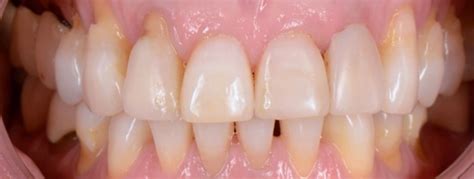

En la práctica odontológica actual, la estética dental juega un papel crucial. La armonía en color y forma de las piezas dentales es altamente valorada. Sin embargo, los odontólogos a menudo se enfrentan a situaciones clínicas complejas al realizar exámenes diagnósticos, especialmente en pacientes que buscan blanqueamiento dental y presentan lesiones en el tercio gingival.

Estas lesiones, caracterizadas por la pérdida de sustancia dental, pueden ser compatibles con la erosión ácida, abfracciones o caries. Además, muchos pacientes experimentan hipersensibilidad ante cambios térmicos o estímulos táctiles. Se estima que millones de personas sufren de sensibilidad dental ocasional o crónica, y un alto porcentaje puede experimentar sensibilidad durante el blanqueamiento dental.

Respecto a la evaluación diagnóstica, apenas a la observación se visualicen clínicamente como erosiones o se evalúe cierto riesgo de una lesión en el tercio gingival, éste debe ser cuantificado con la mayor precisión posible. En todos los casos se debe correlacionar la observación con el relato clínico del paciente relacionado con la sintomatología (tabla 2).

El diagnóstico preciso requiere una historia clínica detallada, explorando factores de riesgo dietéticos, médicos y comportamentales. El examen clínico debe evaluar la textura superficial, el contorno y la presencia de exposición dentinaria. La documentación fotográfica y los modelos de estudio seriados facilitan la detección de cambios progresivos.